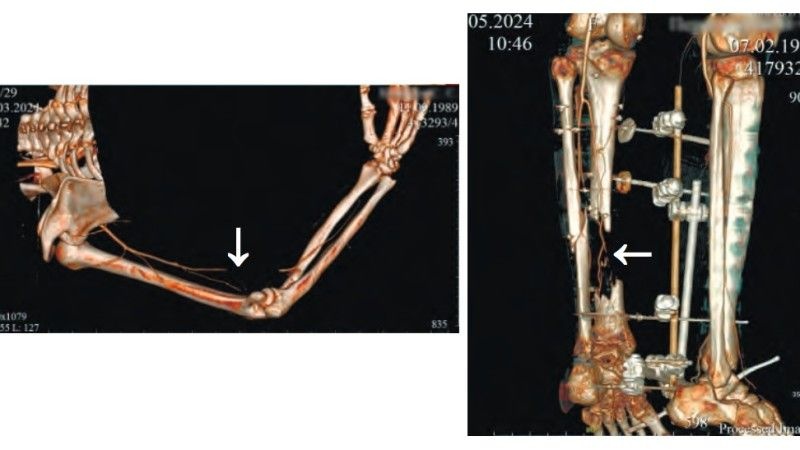

Według danych pochodzących z rosyjskiego „Przeglądu Wojenno – Medycznego” ponad trzy czwarte sanitarnych strat armii rosyjskiej w wojnie pozycyjnej jest spowodowanych atakami ukraińskich, bezzałogowych statków powietrznych. Wniosek ten wyciągnięto po przebadaniu prawie sześciu tysięcy rannych, rosyjskich żołnierzy.